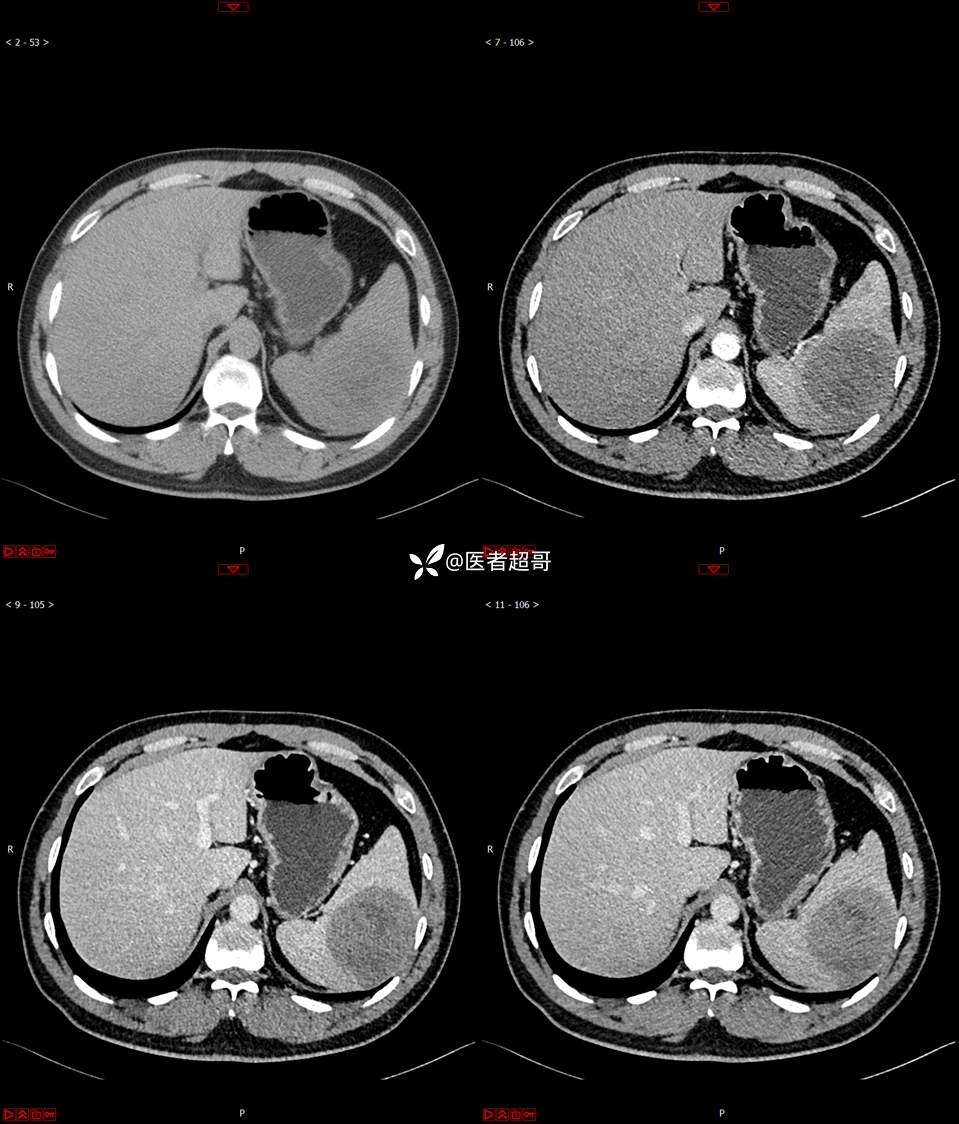

【影诊笔记738】脾脏低密度影,请诊断分析~~

男,33岁 0201215 01

主 诉:发现脾占位2月余。

现病史:患者2月余前体检行肝胆胰脾肾彩超提示脾占位性病变,未予特殊诊治,1天前于区人民医院行肝胆胰脾MR平扫提示脾脏占位性病变,左肾小囊肿,现患者无腹胀、腹泻,无恶心呕吐,无胸闷憋气等症状,今为求进一步治疗,患者来我院就诊,门诊以“脾占位性病变”收入院。患者自发病以来,一般情况可,神志清,精神可,饮食、二便正常,睡眠可,体重体力无明显改变。